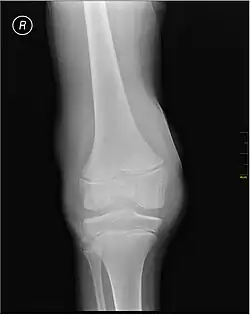

X-ray of Hemarthrosis -

X-ray of Hemarthrosis